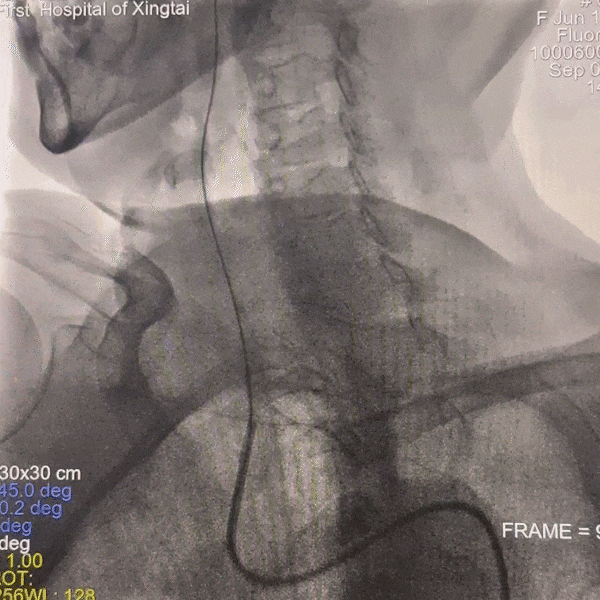

通路建立:患者主动脉弓造影显示Ⅲ型弓,病变为右侧大脑中动脉栓塞,故选择赛诺神畅APEX TRA GC™5F-130 SIM2导引导管同轴长鞘建立通路。

动脉长鞘怎么置入一技之“长”丨经桡及经股困难入路应用赛诺神畅APEX TRA GC™导引导管建立通路病例合集_https://www.jmylbn.com_新闻资讯_第7张

Ⅲ型弓